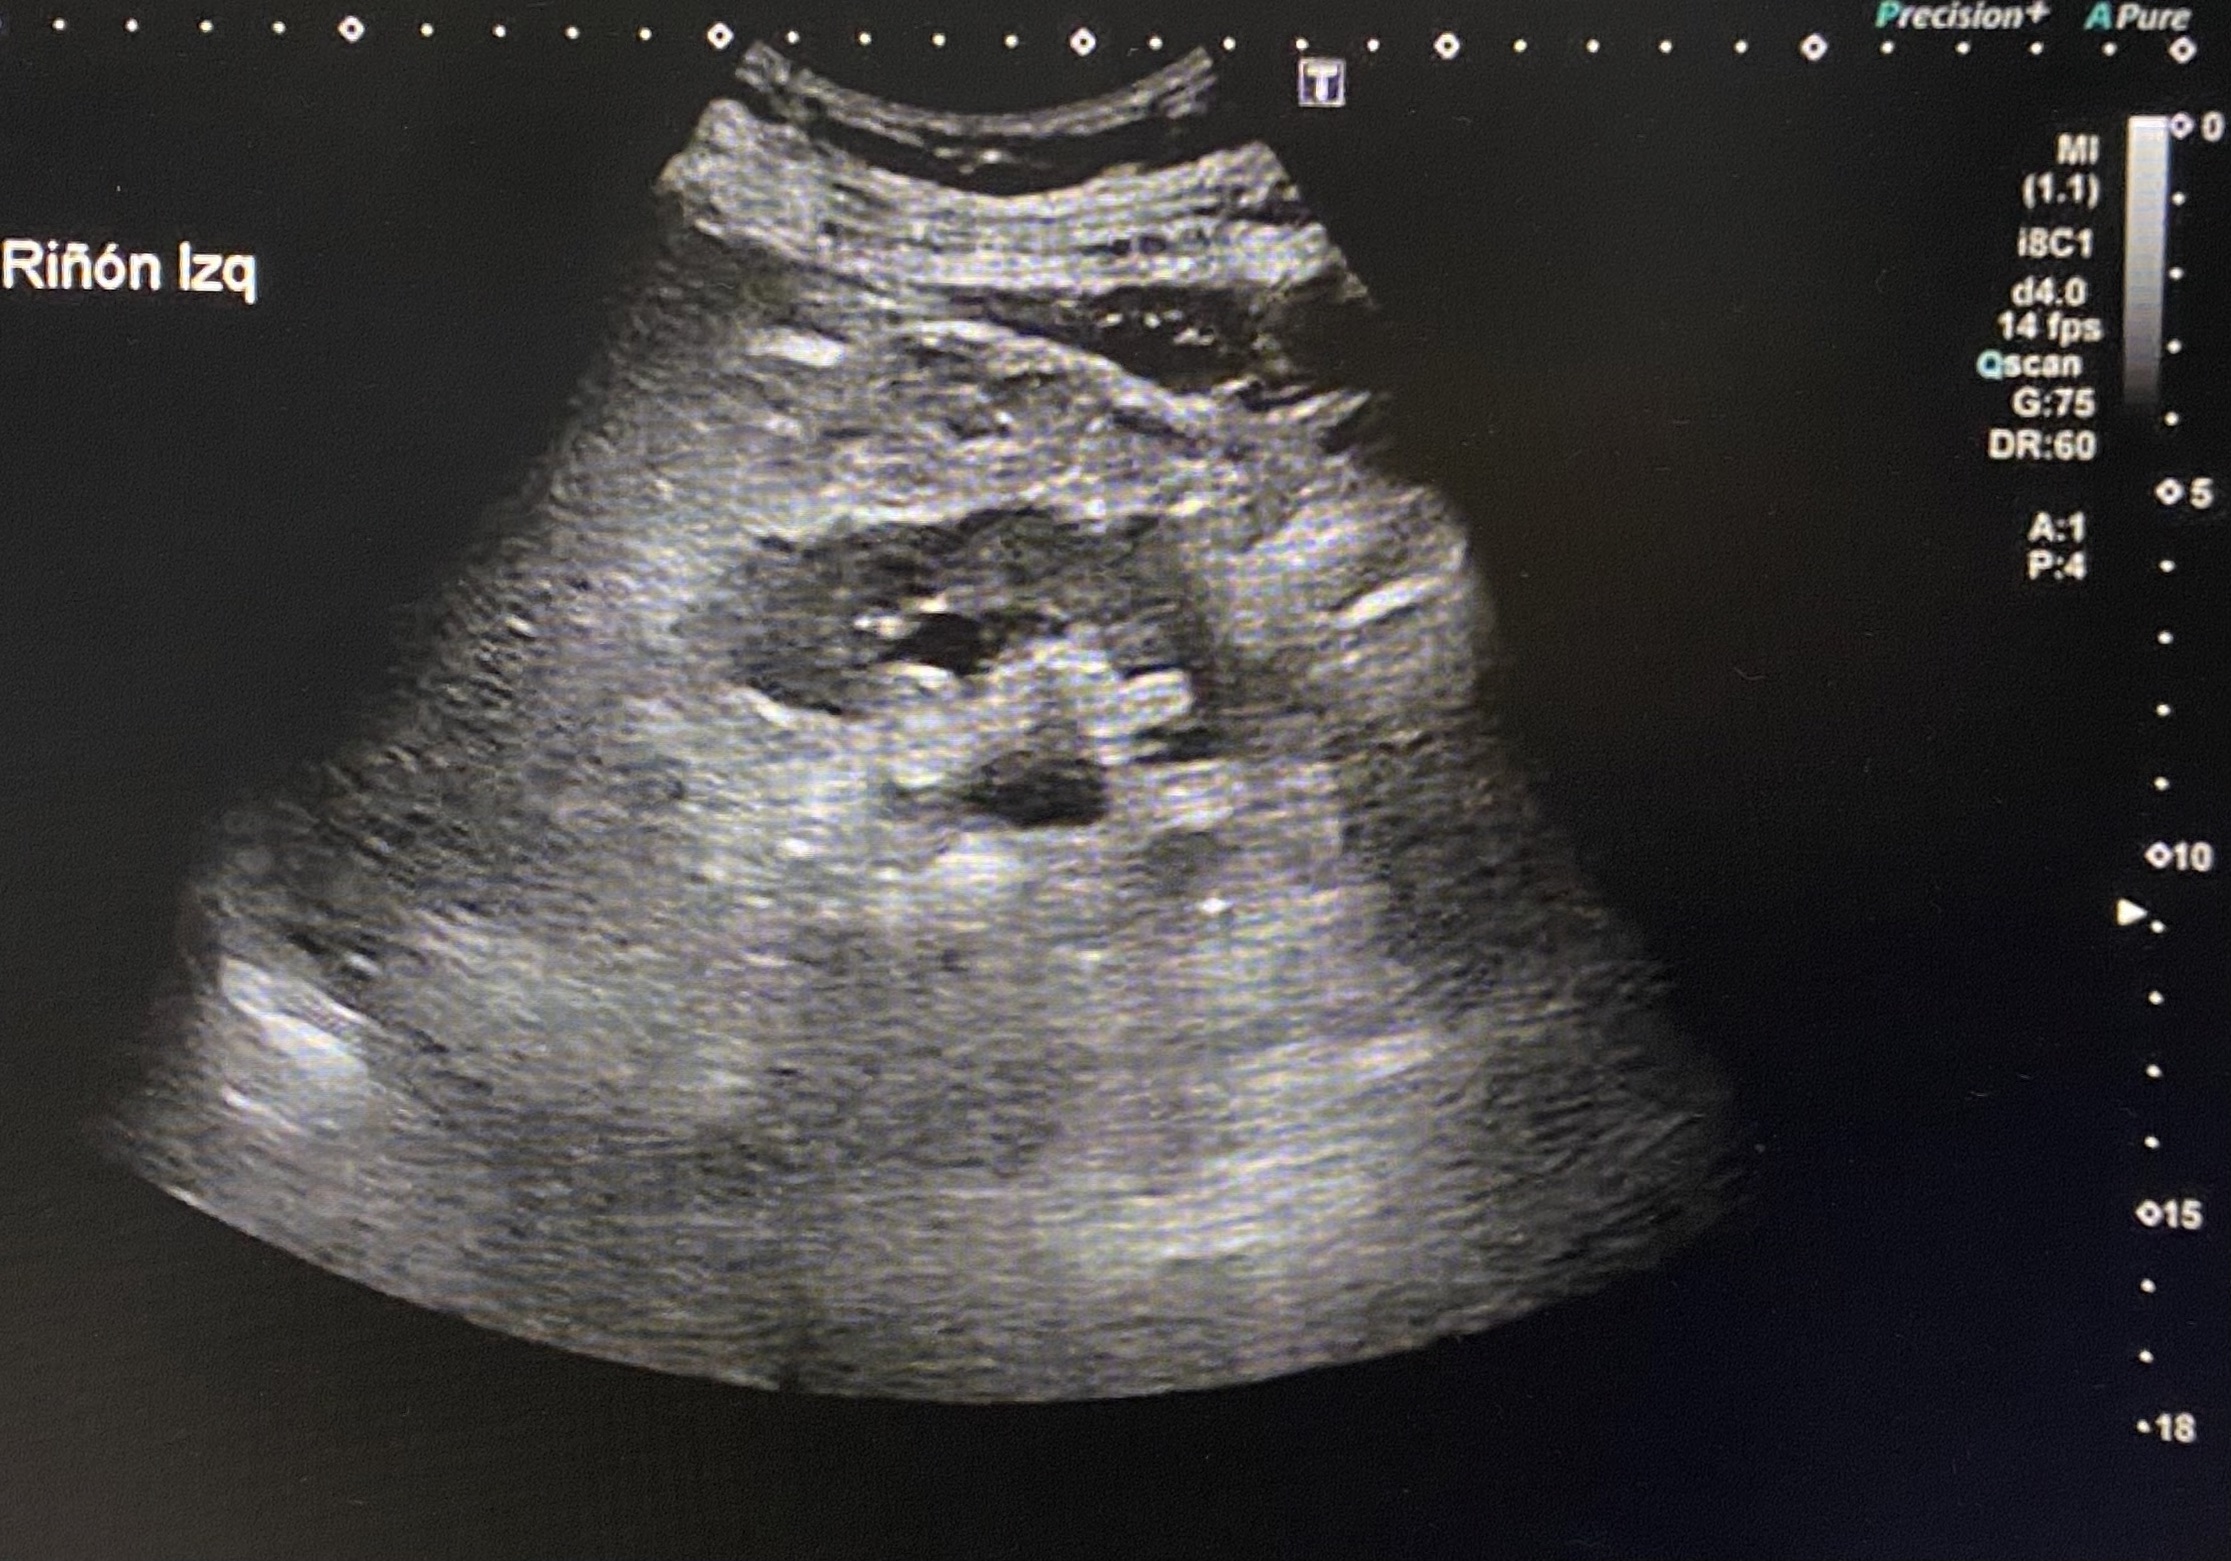

En ecografía de control dos meses después se observa una ligera dilatación pielocalicial del riñón izquierdo y normalidad del derecho (imagen 3), además se consigue objetivar la próstata aumentada de tamaño (imagen 4).